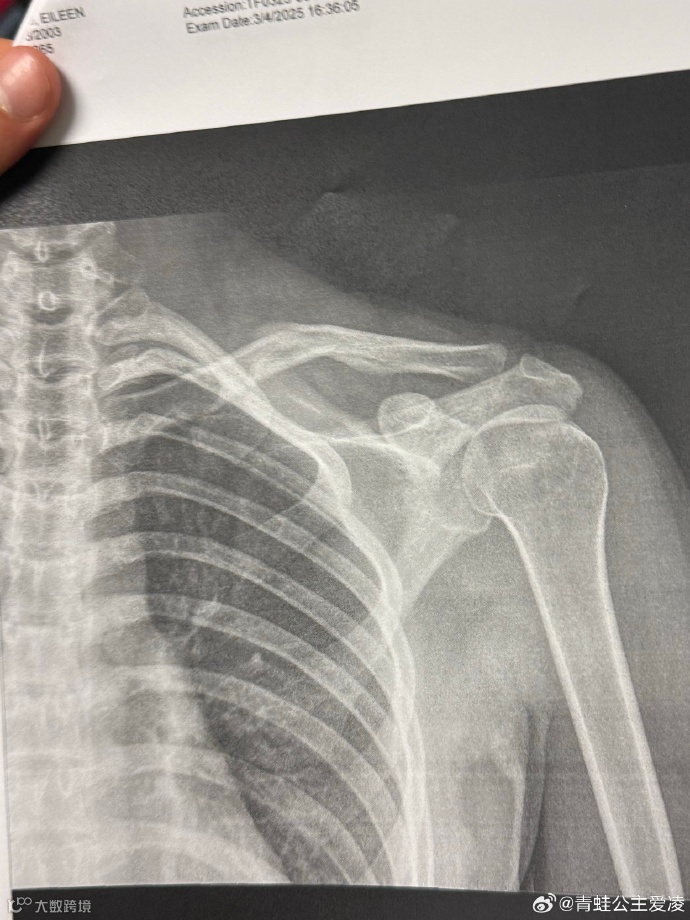

3月9日,中国自由式滑雪名将谷爱凌晒肩部X光片子,并配了一个心碎的表情💔 ,随后相关话题登上热搜。

片子的日期是3月4日,目前尚不得知谷爱凌本次的伤病是新伤还是旧伤。